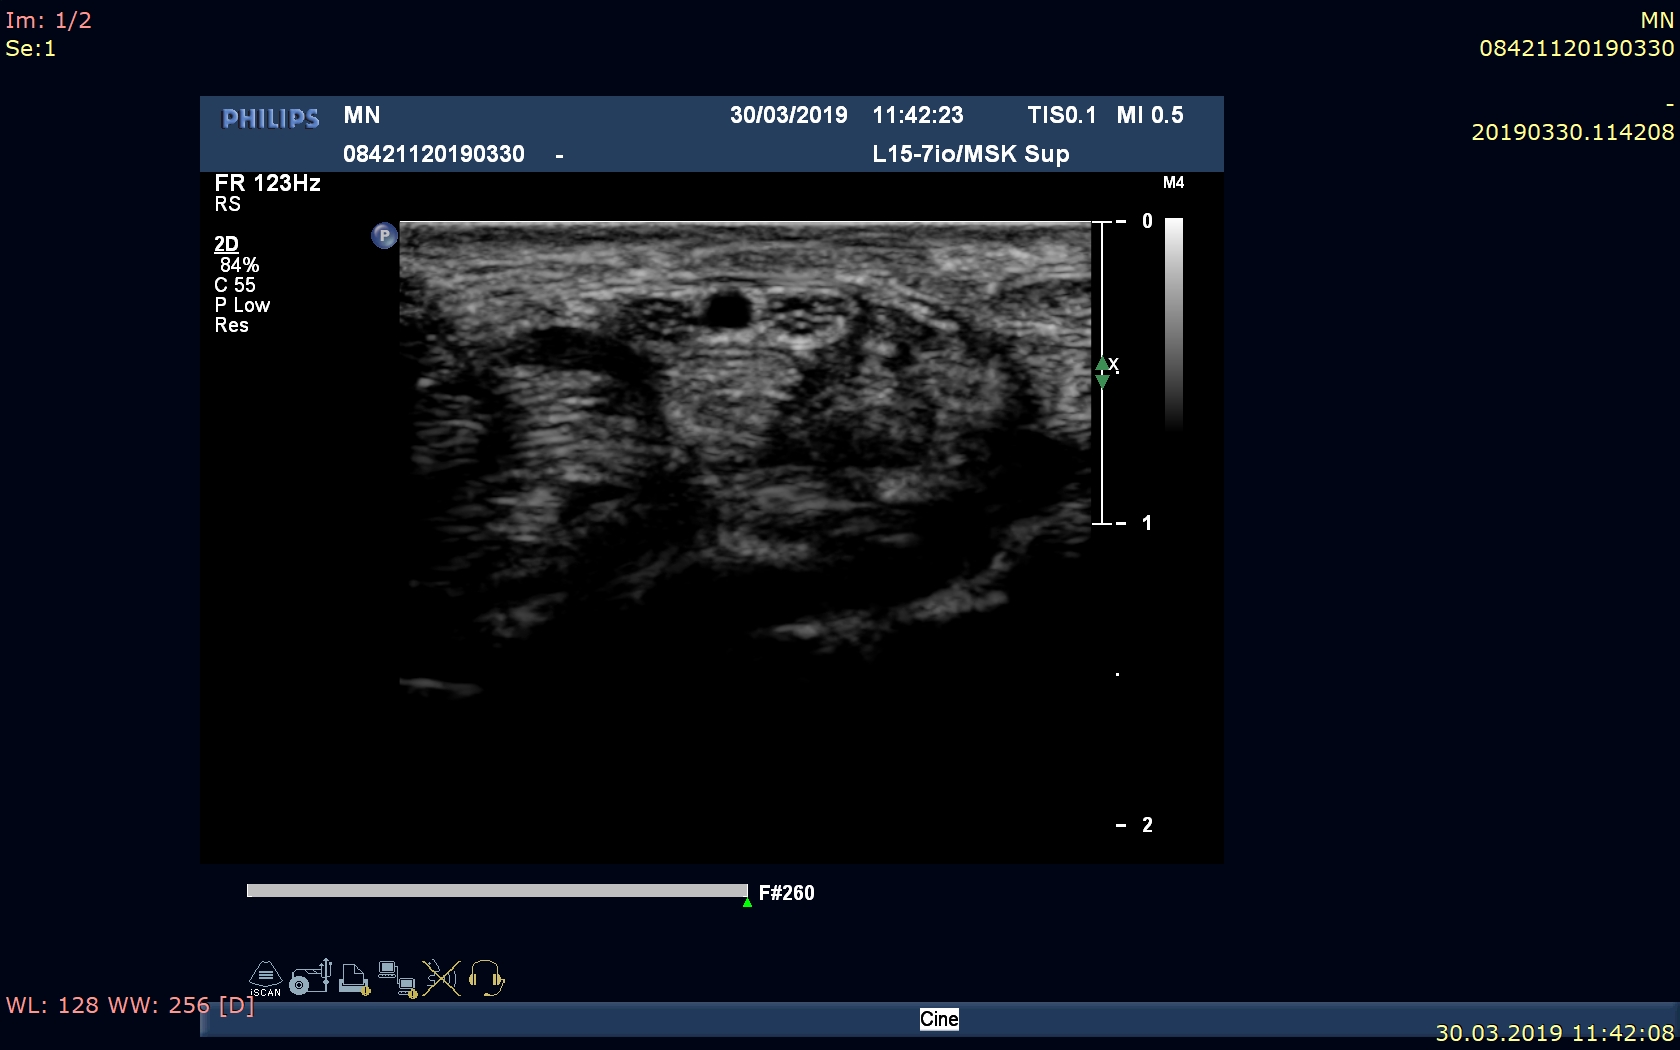

Ból barku podczas unoszenia ręki – aktualnie stan po zabiegu operacyjnym.